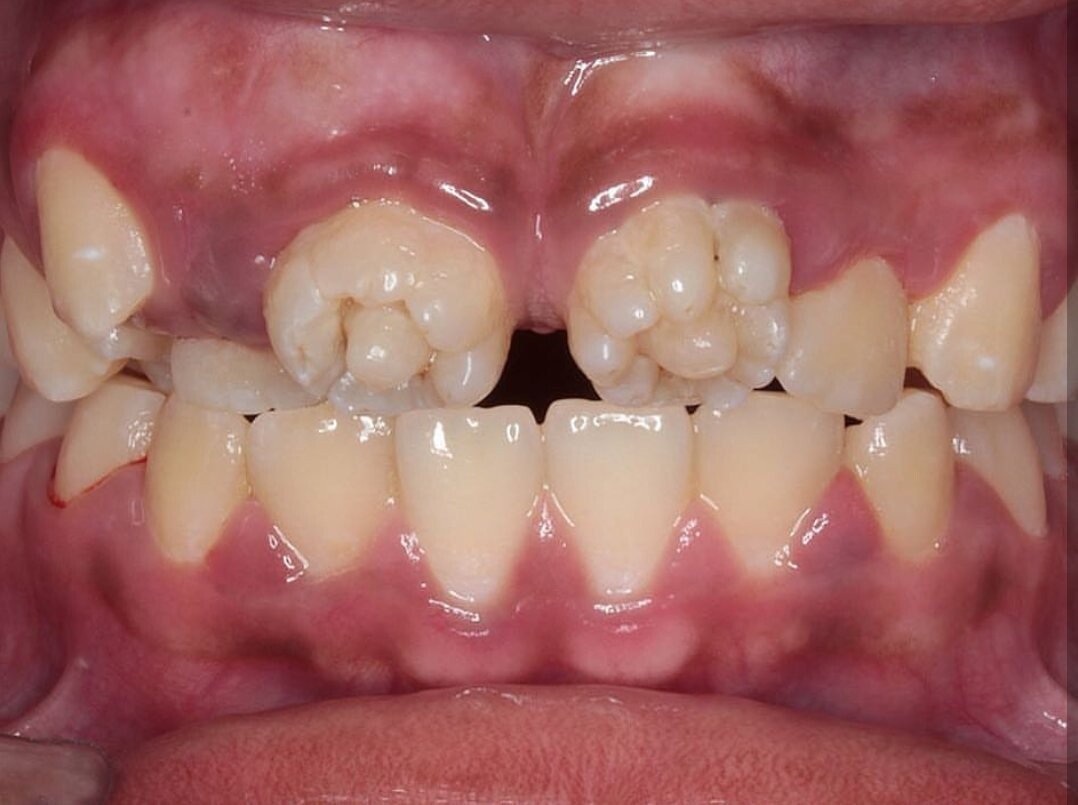

What Are Mulberry Molars?

Mulberries. They sound like something you find in a scrumptious pie or jam. Mulberry molars, on the other hand, are a tough pill to swallow. After your child loses their baby teeth, their permanent teeth come in when they're around 5 or 6. Occasionally these fresh molars are abnormally shaped with small bumps, reminiscent of mulberry fruits, according to the Rutgers School of Dental Medicine. While mulberry molars can be alarming for parents — they can be easily treated.

Often, dentists in developed countries have never treated a case of mulberry molars, notes the Head and Neck Pathology report. But they should be able to identify it as the bumpy surface makes the condition very recognizable. Syphilis is diagnosed via a blood test. Antibodies to the bacteria are present in the blood of those with syphilis. It's a severe condition if passed along to babies — consequently, pregnant women should be tested.